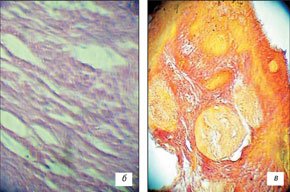

В исследовании отмечена разная степень выраженности деструкции ткани: минимальная (n=2), умеренная (n=2), глубокая (n=17). Слабо выраженная деструкция отмечена при воздействии на ткань силы тока 70-100 мА в течение 10-15 мин. Изменения наблюдались преимущественно в строме, носили очаговый характер, соответствовали фибриноидному набуханию. При умеренной деструкции помимо очагов фибриноидного набухания отмечены изменения железистого компонента в виде кариопикноза и кариорексиса. Умеренные изменения наблюдались при воздействии силы тока 80-90 мА в течение 15 мин. Глубокая деструкция с очагами некротического детрита, распространенным фибриноидным набуханием волокон стромы, разрушением желез, наличием "электрометок" наблюдалась в большинстве случаев исследования. Феномен "электрометки" отмечен в наших предыдущих работах по электрохимическому лизису [1-3]. Применялась сила тока от 90 до 100 мА, время воздействия от 25 до 40 мин в зависимости от размеров и УЗ-семиотики тканей (рис. 4).

а) До лизиса.

б, в) После лизиса.